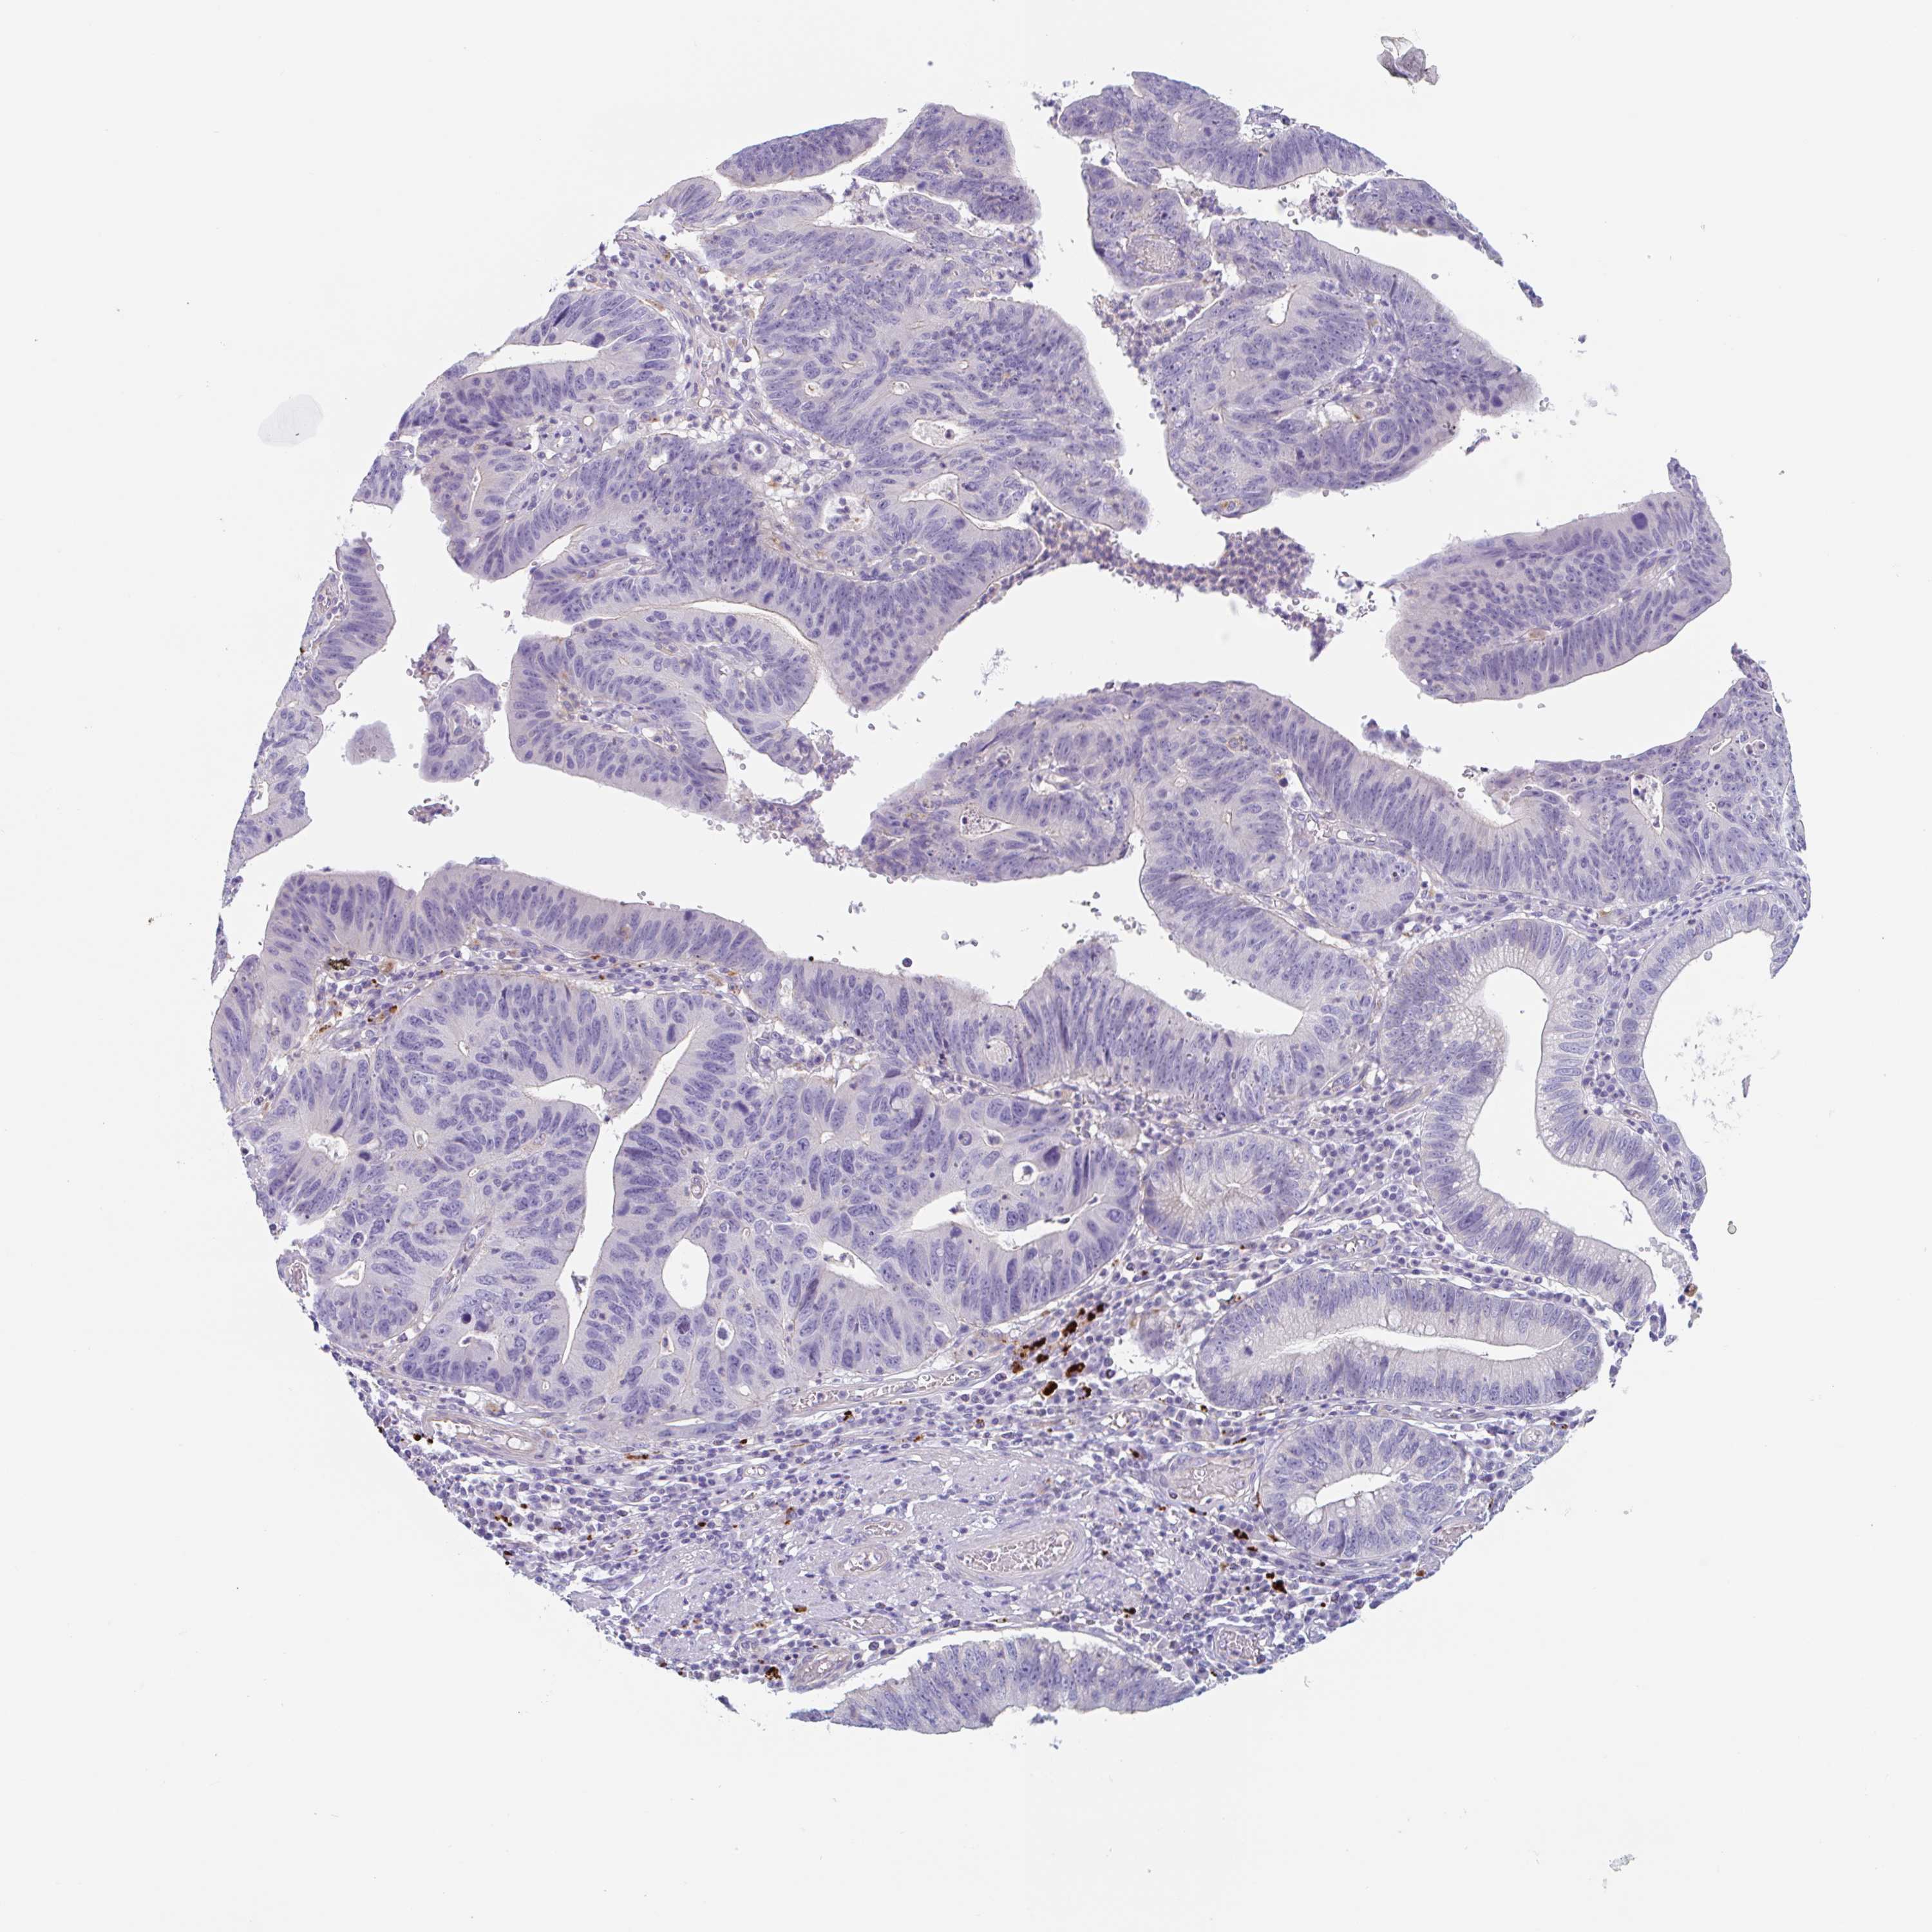

STOMACH CANCER - Protein expressioni

A mouse-over function shows sample information and annotation data. Click on an image to view it in a full screen mode. Samples can be filtered based on level of antibody staining by selecting one or several of the following categories: high, medium, low and not detected. The assay and annotation is described here.

Antibody stainingi

Antibody staining in the annotated cell types in the current human tissue is reported as not detected, low, medium, or high, based on conventional immunohistochemistry profiling in selected tissues. This score is based on the combination of the staining intensity and fraction of stained cells.

Each image is clickable and will lead to virtual microscopy that enables deeper exploration of all samples and also displays staining intensity scores, fraction scores and subcellular localization as well as patient and tissue information for each sample.

Antibody HPA051671

Antibody HPA053556

Staining

High

Medium

Low

Not detected

Intensity

Strong

Moderate

Weak

Negative

Quantity

>75%

75%-25%

<25%

None

Location

Nuclear

Cytoplasmic/membranous

Cytoplasmic/membranous,nuclear

Adenocarcinoma, NOS